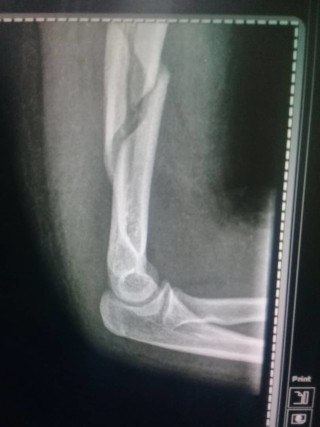

Foto tomada por @hmorillo2021 con Samsung J2 Prime (Es el de mi esposa). Ya saben cómo se nos puso el corazón al ver esa imagen.

Lamentablemente, en mi caso no ha sido posible estar tan activo como quisiera debido a una urgencia que tuve que atender con mi hija: Se fracturó el brazo y fue todo un proceso buscando en entes públicos donde hacer las placas de rayos X. En un ente privado son unos 60 dólares, porque además hay que hacer placa de nuevo una vez se coloca el yeso. Unos 290 STEEM incluyendo material y medicación.